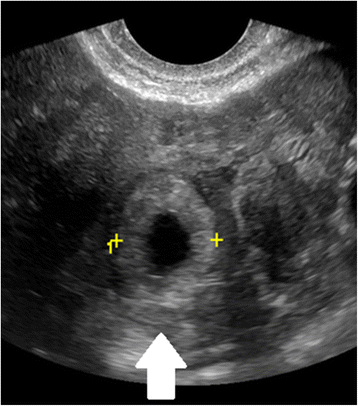

Diagnostic criteria for a cesarean scar EP by ultrasound include visualization of the gestational sac at the site of the prior hysterotomy (Fig. 7), outside the endometrial cavity [104]. The myometrium should be very thin (1–3 mm) or absent between the gestational sac and the bladder (Fig. 8). A negative ‘sliding organ’ and the presence of peripheral Doppler flow are expected [9].